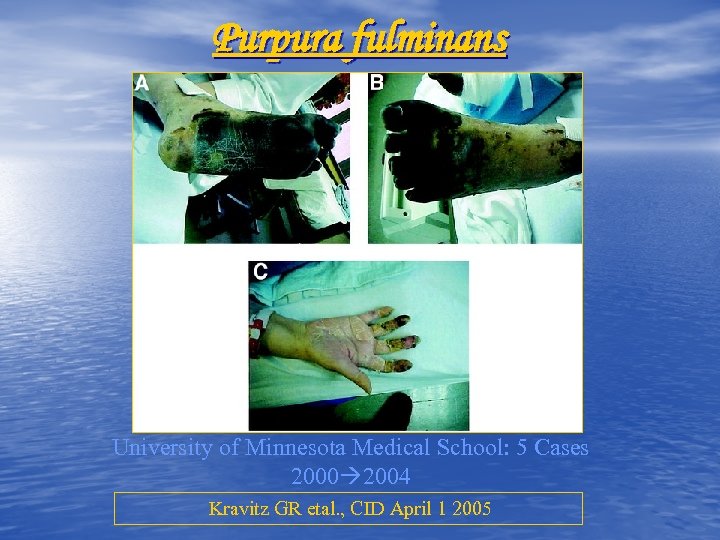

Purpura fulminans University of Minnesota Medical School: 5 Cases 2000 2004 Kravitz GR etal. , CID April 1 2005

Purpura fulminans University of Minnesota Medical School: 5 Cases 2000 2004 Kravitz GR etal. , CID April 1 2005

Purpura fulminans University of Minnesota Medical School: 5 Cases 2000 2004 Kravitz GR etal. , CID April 1 2005

Purpura fulminans University of Minnesota Medical School: 5 Cases 2000 2004 Kravitz GR etal. , CID April 1 2005